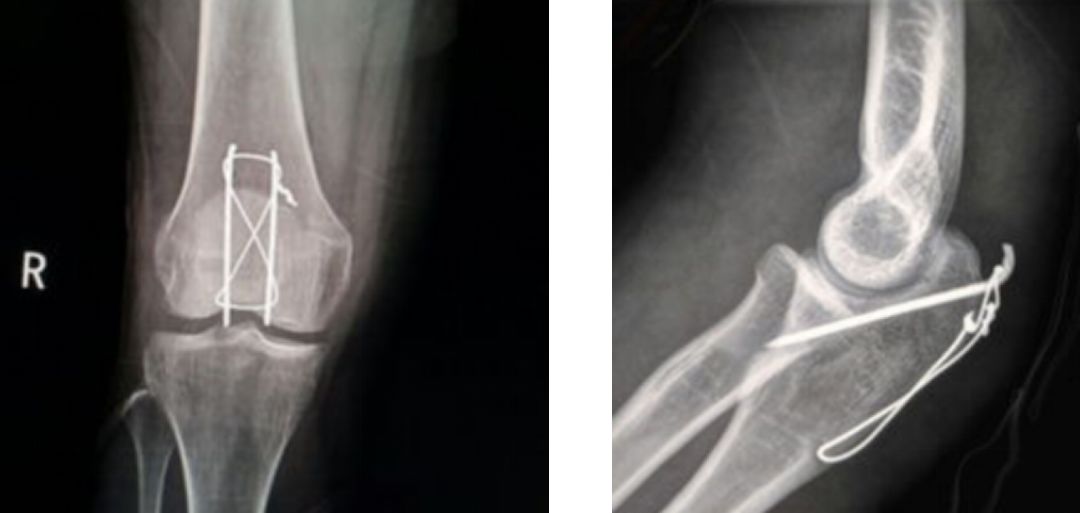

9、克氏针的阻挡作用

石墨法:对于伸肌腱止点撕脱骨折型的锤状指,利用克氏针的阻挡作用,可以将末节基底背侧的骨折块复位并卡压固定。

改良版石墨法:改良的石墨法,利用的是克氏针的弹性原理巧妙地将远位指间关节背伸,这样操作更利于骨折的愈合。